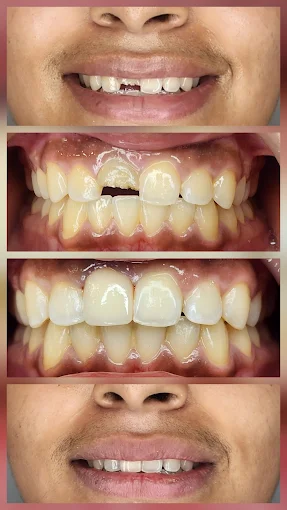

3.Patient transformation portfolios and before-after documentation provide valuable insights into the dentist in Delhi capabilities and typical outcomes. Reputable practices readily share transformation examples and maintain transparent outcome records.